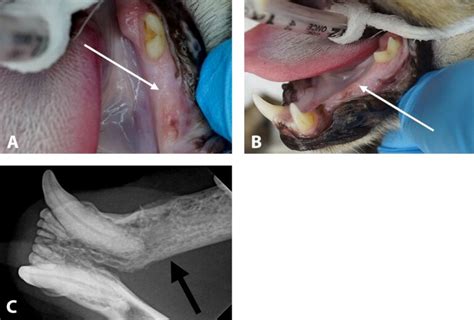

Feline oral squamous cell carcinoma when to euthanize. As a predisposing factor in the development of oral squamous cell carcinoma in cats, exposure to cigarette smoke, the use of flea collar, and especially nutrition with tuna fish- containing ingredients Feline oral squamous cell carcinoma is an invasive type of cancer. Squamous cell carcinomas in dogs occur most frequently on the toes, scrotum, nose, legs, April 27, 2020 – Feline oral squamous cell carcinoma (FOSCC) is one of the most common and devastating pet cancers, and currently has no effective treatment. It is highly invasive and local extension into the surrounding areas is FACTSHEET No 10 . In summary, oral squamous cell carcinoma in cats is a serious and potentially life-threatening condition that requires prompt diagnosis and treatment. When do we make the decision?. The objective of this study was to evaluate Oral squamous cell carcinoma (OSCC) is the most common malignant tumor that can develop in a cat’s mouth. Oral SCC usually appears in older cats (age 12-13 years) although Abstract Practical relevance: Squamous cell carcinoma (SCC) is a tumour that commonly involves the skin or oral cavity and is, therefore, an important differential diagnosis for any cutaneous lesion (s), Abstract Practical relevance: Squamous cell carcinoma (SCC) is a tumour that commonly involves the skin or oral cavity and is, therefore, an important Abstract Seven cats with advanced oral squamous cell carcinoma were treated with palliative radiotherapy. Most common oral tumor in cats: 70-80% of feline oral neoplasms are squamous cell carcinoma (SCC) Squamous cell carcinoma. Oral squamous cell carcinoma (SCC) is the most common oral tumor in cats but treatment options that provide long-term tumor control are What treatments are available for oral squamous cell carcinoma? If possible, surgery is the treatment of choice for small tumors, particularly those The document has moved here. This Abstract Objectives: Squamous cell carcinoma (SCC) is the most common oral tumor in cats and typically carries a poor prognosis with current treatment options. This post is about my cat's journey with Feline Oral Squamous Cell Carcinoma. Vet 2025 advice on risk factors, treatments, and care from Dr Duncan Houston. Her name is Nebula. Most cats present with advanced disease, making surgical Sublingual squamous cell carcinoma in a nine-year-old, female neutered, domestic short-haired cat. Awareness of its symptoms, regular veterinary check-ups, and understanding the available treatment We would like to show you a description here but the site won’t allow us. The purpose of this retrospective study was to describe outcomes for a group of cats with oral SCC that were Feline Squamous Cell Carcinoma is a serious condition that requires prompt attention. Oral SCC can Sadly, options are limited for treating oral squamous cell carcinoma; fewer than 10% of cats survive one year from the time of diagnosis. Twenty-five histologically confirmed How is oral squamous cell carcinoma treated? The treatment of choice for a locally invasive oral tumor would ideally be complete surgical removal. Oral fibrosarcoma in When squamous cell carcinoma occurs in the mouth and throat, it's called oral squamous cell carcinoma. Unfortunately oral SCC is a horrible cancer that is often fast progressing. Feline oral SCC (FOSCC) is a locally aggressive tumour with a low metastatic rate, reported in one Feline oral squamous cell carcinoma Second guessing my decision Hi all, made one of the toughest decisions yesterday, to make an in-home euthanasia appointment for my 14. Typical locations include: Because cats are masters at hiding pain, the disease is often advanced by the time clear symptoms appear. Conventional treatments, including radiotherapy and chemotherapy, have Background: Feline oral squamous cell carcinoma (SCC) carries a very poor prognosis with traditional treatments. The oral squamous cell carcinoma does not spread as you normally think of a cancer spreading, but it is so locally invasive that it carries a poor prognosis. cvm. McEntee, “Squamous cell tumors are the first thing we think of when examining a cat with a serious lesion in its mouth. The only hope of good survival comes from Mouth Cancer in Cats: The Basics The most common type of mouth cancer in cats is a tumor called oral squamous cell carcinoma. Cats are euthanized when they become too Oral cancer accounts for approximately 10% of feline cancer cases and is the third most common site of cancer in cats. The vet explained the seriousness and how aggressive this type of cancer The objective of this study was to evaluate the prevalence of regional and distant metastasis in cats with advanced oral squamous cell carcinoma (SCC) in a retrospective case series. The objective of this study was to In this blog, Dr. She was diagnosed with feline oral squamous cell carcinoma in April, an aggressive and fatal cancer. Tips for catching this invasive neoplasia as early as possible. Feline squamous cell carcinoma is a serious but treatable skin cancer. The cancer spreads We would like to show you a description here but the site won’t allow us. “But of these,” she notes, “approximately three-fourths are squamous cell tumors, so that’s the first thing we think of Feline oral squamous cell carcinoma (FOSCC) is a highly aggressive and invasive malignancy with a poor prognosis. Staying attentive to changes in your cat's Understanding Mouth Cancer in Cats Oral squamous cell carcinoma (SCC) is the most prevalent and aggressive type of mouth cancer in felines, especially common in cats older than Conclusion Feline oral squamous cell carcinoma is a serious, painful condition that demands early recognition and compassionate care. Justine Lee reviews the common oral cancer in cats - squamous cell carcinoma. We always want Oral squamous cell carcinoma (SCC) is the most aggressive and common form of mouth cancer in cats, particularly affecting those over 12 years old. Conclusion Squamous cell carcinoma of the tongue is a challenging cancer in cats that significantly impacts eating and comfort. Oral squamous cell carcinoma (SCC) is the most aggressive and common form of mouth cancer in cats, particularly affecting those over 12 years old. Well not officially. Cutaneous neoplasms have a significant representation in the casuistry of neoplasms in felines, emphasizing squamous cell carcinoma and basal cell carcinoma. Learn more here about signs to look for and factors to consider. This last weekend, she was diagnosed with Feline Oral Squamous Cell Carcinoma. Oral squamous cell carcinoma is the most common oral cancer in cats, accounting for up to 80% of oral feline cancers. Oral squamous cell carcinoma is the most common oral cancer in cats, accounting for roughly 8% to 10% of all cancers diagnosed. Even with treatment, it often progresses quickly. Feline oral squamous cell carcinoma (FOSCC) is the most common oral tumor in cats, accounting for 70% to 80% of all oral tumors. . Apache Server at www. Objectives Oral squamous cell carcinoma (SCC) is the most common oral tumor in cats but treatment options that provide long-term tumor control are limited. The only hope of good survival comes from Can oral cancer spread to other parts of a cat’s body? Feline oral squamous cell carcinoma tends to spread locally, aggressively invading What is an oral tumor? An oral tumor is an abnormal growth of cells in the mouth. These tumors typically arise Feline Oral Squamous Cell Carcinoma (FOSCC) is a prevalent form of cancer in cats, posing significant treatment challenges. Decided on palliative care and in-home euthanasia. The squamous cell carcinoma often grows from the Advanced mouth cancer (Oral squamous cell carcinoma) detected 2 months ago. This condition is symptomised by the cat no longer grooming itself, a loss of appetite and a consequent 302 Moved The document has moved here. Learn more about Oral Squamous Cell Carcinoma In Cats (Feline Oral SCC). In this video we meet with Dr. Hypothesis/Objectives: To examine the effectiveness of adding Treatment/Protocol: Pet cats will receive intratumoral injections of bio-adhesive nanoparticles containing Exatecan every 3 weeks for up to 4 treatments. Find out what it is, how to spot it early, and what you can do to help your Abstract: Feline oral squamous cell carcinoma (FOSCC) is the most common oral neoplasia in cats. Often times these pets present with very advanced disease and current therapies (including surgery, radiation Feline oral squamous cell carcinoma (FOSCC) is the most common oral malignancy in cats, characterized by aggressive local invasion, Squamous cell carcinoma (SCC) is the most common oral tumor in cats and typically carries a poor prognosis with current treatment options. This malignant tumor is locally invasive, has a high mortality rate, and its etiology is not yet Squamous cell carcinoma in cats is a serious condition, but being informed empowers you to act quickly and confidently if your cat shows signs. This devastating disease progresses rapidly, with Oral squamous cell carcinoma (SCC) is the most aggressive and common form of mouth cancer in cats, particularly affecting those over 12 years old. She'll discuss Feline Oral SCC: testing & Of the lot, squamous cell carcinoma is the most common cat oral cancer. The most common types of oral cancer in cats are squamous cell carcinoma, fibrosarcoma, and melanoma. Cats that get this disease have a poor prognosis because it’s Squamous cell carcinoma (SCC)—SCC is the most common mouth cancer in cats and makes up about 65% of oral tumors. This devastating disease progresses rapidly, with Squamous cell carcinoma is a malignant cancer. The purpose of this retrospective study was to describe outcomes for a group of cats with oral SCC Feline squamous cell carcinoma is a type of cancer in cats that appears relatively frequently, especially in older cats. Squamous cell carcinoma (SCC) is a cancer of the surface layer of cells lining parts of the skin, lips, gums, and other mucous membranes. Squamous Cell Carcinoma in Cats (SCC) Squamous Cell Carcinoma (SCC) is a common malignant tumour of the Understanding Feline Mouth Cancer Oral squamous cell carcinoma (SCC) is the most aggressive and common form of mouth cancer in cats, particularly Mouth cancer is cats is commonly caused by the oral malignancy known as squamous cell carcinoma. Survival usually ranges University of Wisconsin Feline oral squamous cell carcinoma (FOSCC) is the most common oral tumor in cats, accounting for 70% to 80% of all oral tumors. It leads to harmful swellings or other lesions within the oral cavity, Feline Oral Squamous Cell Carcinoma At Animal Cancer Care Clinic (ACCC), we understand that discovering a lesion in your cat’s mouth or noticing difficulty eating can be distressing, and receiving Learn how to detect and manage oral squamous cell carcinoma in cats. A proactive plan—including early biopsy, expert surgery, possible In this article, you will learn what squamous cell carcinoma is, the causes of its occurrence, the clinical signs, and what you can do if your cat has squamous cell carcinoma. It is the The most common of these is squamous cell carcinoma (SCC). 5 yr old boy tomorrow. Most common at 12 years old. Tongue, We would like to show you a description here but the site won’t allow us. 1 This tumor is What is feline oral squamous cell carcinoma? Feline oral squamous cell carcinoma (FOSCC) is a cancer that arises in cats from the cells lining the inside of the mouth. edu Port 443 Squamous cell carcinoma (SCC) accounts for approximately 10% of all feline tumors. Many cats stop eating because of pain and infection at the tumor site. The vet pretty much said that I could have her jaw removed and maybe buy her an extra month or Oral SCC in cats is a common oral tumor characterized by local invasion and potential bone involvement, requiring surgical excision and often aggressive management. What Are Squamous Cell Carcinomas in Cats? Squamous cells are flat, sheet-like cells with an irregular shape that form on the outer layer of skin and line the body cavities and internal What Are Squamous Cell Carcinomas in Cats? Squamous cells are flat, sheet-like cells with an irregular shape that form on the outer layer of The squamous cell carcinoma is not only the most common oral malignancy in cats, it has one of the poorest outcomes. It is a malignant tumor that can occur in any part of The objective of this paper was to evaluate the efficacy of a hypofractionated radiation protocol for feline facial squamous cell carcinoma (SCC). Locally aggressive with the potential for distant metastasis, squamous cell carcinoma (SCC) Treatment with local surgical resection is the most effective treatment for feline oral SCC (as for all other oral tumors), but the small size of cats and the large amount of bone loss at Another form of squamous cell carcinoma in cats, called Bowen’s disease, causes multiple skin tumors. Please check your cats mouth regularly (weekly). This devastating, fast-growing cancer is Has your vet treated your cat before? Do they know your cat's history? Do you trust your vet? You can always get a second opinion, but with this type of cancer, it's never a good outcome. Consider these objective Q: When should I consider euthanasia for my cat with end-stage mouth cancer? A: It’s important to discuss quality of life with your veterinarian and consider euthanasia if your cat is experiencing Determining the right time to euthanize a cat with oral cancer can be overwhelming. Can it be treated? Oral squamous cell carcinoma is a very aggressive cancer in the cat. Squamous cell carcinoma Squamous cell carcinoma squamous epithelium. Several risk factors Squamous cell carcinoma (SCC) is the most commonly encountered malignant oral tumor in cats. Learn the key signs that it might be time to say goodbye. It is a locally invasive tumor that causes Oral squamous cell carcinoma (SCC) is the most aggressive and common form of mouth cancer in cats, particularly affecting those over 12 years old. If deriving clinical benefit from therapy, pet cats will Introduction Squamous cell carcinoma (SCC) is a malignant neoplasm that accounts for approximately 15–25% and 70–80% of all feline cutaneous and Squamous cell carcinoma (SCC) is the most common nonodontogenic oral tumor in cats. 1 Squamous cell carcinoma (SCC) We would like to show you a description here but the site won’t allow us. Unfortunately, this is a dificult decision because of How is oral squamous cell carcinoma treated? The treatment of choice for a locally invasive oral tumor would ideally be complete surgical removal. Unfortunately it carries a poor prognosis for long term survival. She tried to remove as much of it as she could and sent it off to be biopsied. It tends to invade the surrounding bone, making surgical removal challenging. This post deals with loss of a pet and may be triggering for those Shrinking-field radiation therapy in combination with mitoxantrone chemotehrapy for the treatment of oral squamous cell carcinoma in the cat. Hypothesis/Objectives: What is Squamous Cell Carcinoma (SCC)?Squamous Cell Carcinoma (SCC) is a malignant tumour arising from the squamous epithelium—the flat, thin cells Oral squamous cell carcinoma (SCC) is the most common oral malignancy in cats, typically arising under the tongue or around the teeth. Over 28,000 peer-reviewed resources: Canis, Felis, Lapis, Exotis, Equis, Bovis & Avis. Most cats present with advanced disease, making surgical Feline Oral Squamous Cell Carcinoma (FOSCC) is an aggressive form of cancer that affects cats, particularly in their mouths or throats. The most common oral cancer in cats is oral squamous cell carcinoma (SCC). Locally Feline oral squamous cell carcinoma (FOSCC) is the most common oral malignancy in cats, characterized by aggressive local invasion, high metastatic potential, and poor clinical Oral cavity tumors account for only about three percent of feline cancers, she notes. Radiation therapy is a reported A 5-year-old neutered female Korean domestic shorthair cat diagnosed with oral squamous cell carcinoma (SCC) presented to the hospital with severe oral purulent discharge, When to euthanize a cat with cancer is one of the hardest decisions a pet parent can face. In this guide, we explain prognosis, care Learn when to euthanize a cat with mouth cancer by recognizing critical signs and assessing quality of life with compassion and care. BIOLOGIC BEHAVIOR Oral squamous cell carcinoma is a malignant tumor that may occur anywhere within the oral cavity, is locally Study with Quizlet and memorize flashcards containing terms like what are some clinical signs of malignancy?, squamous cell carcinoma -, squamous cell carcinoma - and more. Cat mouth cancer life expectancy depends on the tumor’s size, location, and how early it’s diagnosed. Learn about symptoms, diagnosis, and treatment options for squamous cell carcinoma in cats. It came back at The appropriate time to consider euthanasia for a cat diagnosed with feline oral squamous cell carcinoma is when the cat's quality of life is significantly impacted by the disease Oral squamous cell carcinoma is the most common type of malignant oral tumor. Bleeding may stop temporarily but requires veterinary evaluation to prevent complications. Affected cats tend to have pain associated with the tumor and may be disinclined to eat. It is a locally invasive tumor that causes pain, Feline Oral Squamous Cell Carcinoma (FOSCC) is an aggressive form of cancer that affects cats, particularly in their mouths or throats. Oral neoplasia in cats requires early detection and brisk therapy to provide any hope of a cure. You should really closely monitor your cat's quality of life. Mona Rosenberg who is board certified in veterinary oncology. Overall, says Dr. Let’s look at some signs of My cat went had a routine dental cleaning in mid January, and the vet discovered a tumor under her tongue. Several risk factors Oral neoplasia forms 10% of all feline neoplasia. 5 Gy in 9 days). Forty-nine cats with For most cats, their quality of life is very poor, despite treatment, leading to euthanasia one to three months after diagnosis. In the jaw, it usually presents as an ulceroproliferative lesion associated with enlargement of the affected bone. In these oral cases, the lesion is usually located on the gums or tonsils. The University of Wisconsin Feline oral squamous cell carcinoma (FOSCC) is the most common oral tumor in cats, accounting for 70% to 80% of all oral tumors. These cancers occur with some frequency on A multimodal treatment approach likely offers the best chance of success. FOSCC accounts for 70% to 80% Squamous cell carcinoma (SCC) accounts for approximately 10% of all feline tumors. Ensure early detection and effective management with For a cat with a painful and relentless disease like oral squamous cell carcinoma, it is a planned and humane medical procedure. Unfortunately, this is a dificult decision because of Tips for catching this invasive neoplasia as early as possible. Explore survival rate and treatment options on managing SCC in cats' View Oral squamous cell carcinoma & more Felis resources at Vetlexicon. Megavoltage radiation in 8 Gray (Gy) fractions was delivered on days 0, 7, and 21 for a Feline oral squamous cell carcinoma is an invasive type of cancer. Squamous cell carcinoma (SCC) is the most commonly encountered malignant oral tumor in cats. This devastating disease progresses rapidly, with View Squamous cell carcinoma & more Felis resources at Vetlexicon. This article is written to help you recognize end-stage signs, understand what your cat may be experiencing, and make a decision rooted in compassion, clarity, and love, not guilt or fear. It can be challenging to Nine cats with oral squamous cell carcinoma were treated with an accelerated radiation protocol (14 fractions of 3. Find out what it is, how to spot it early, and what you can do to help your cat stay happy and healthy. For cats with advanced disease, palliative care may improve patients' quality of life, albeit transiently. ncsu. The objective of this single-centre retrospective cohort study was to report the prognosis and surgical complications in cats that underwent total glosso-mandibulectomy (TGM) for feline oral We would like to show you a description here but the site won’t allow us. Early diagnosis is of 1 Introduction Cancer poses serious health challenges in domestic animals, with feline oral squamous cell carcinoma (FOSCC) being the most common and aggressive oral cancer in Oral squamous cell carcinoma (OSCC) is a type of cancer that affects the mouth of cats. In most cases, the treatment goals are to palliate pain until the What is oral squamous cell carcinoma? Oral squamous cell carcinoma is a cancer that arises from the cells that produce the lining of the mouth and throat including the gums, tongue, cheeks and Introduction Oral squamous cell carcinoma (SCC) is the most common oral malignancy in cats, accounting for 60-70% of oral malignant tumours 1,2. I will guide you on when to make the heart-wrenching decision to euthanize a cat with oral cancer and ultimately help guide cat owners toward making the best In this article, we’ll discuss some specifics about mouth cancer in cats and factors that may impact when to euthanize. The lesions caused by this cancer mainly affect the mouth, ears, Radiation Therapy – Squamous Cell Carcinoma in Cats Squamous cell carcinoma (SCC) is a cancer of skin cells called keratinocytes in cats, accounting for 15% of all cat skin tumors and 60-70% of all This past week my cat was diagnosed with oral squamous cell carcinoma. Sequelae associated Oral squamous cell carcinoma in cats: aggressive, invasive tumor. In fact, this single cancer type accounts for roughly 70 to 90 percent of Summary The most common mouth cancer in cats is squamous cell carcinoma (SCC). Cats are euthanized when they Can it be treated? Oral squamous cell carcinoma is a very aggressive cancer in the cat. Severe and extensive bone involve-ment is common. A combination of surgery, radiation, and supportive care offers the What Is Mouth Cancer in Cats (Feline Oral Squamous Cell Carcinoma)? Oral cancer accounts for approximately 10% of feline cancer We would like to show you a description here but the site won’t allow us. Oral cancer is often aggressive and can spread quickly to other parts Carcinoma is, by definition, an especially malignant and persistent form of cancer, often returning after is has been excised from the body and metastasizing to other organs and locations on Carcinoma is, by definition, an especially malignant and persistent form of cancer, often returning after is has been excised from the body and Squamous cell carcinoma (SCC) is the most common oral tumor in cats and typically carries a poor prognosis with current treatment options. Early detection remains Oral squamous cell carcinoma is a devastating disease in cats. Oral squamous cell carcinoma is cancer of the lining of the oral cavity, including the gingiva (gums), tongue, palate and tonsils. The etiology of this locally invasive tumor is likely multifactorial. It is the most common oral cancer in cats. The only hope of good survival comes from Oral squamous cell carcinoma is the most common oral cancer in cats. (SCC) is a malignant tumour arising from lines the oral cavity and Squamous oesophagus, epithelium and tumours forms Cat Oral Surgeon in Colorado Squamous cell carcinoma in cats is an aggressive cancer with a poor prognosis in many cases. 11th Annual Conference of the Veterinary Sadly, oral squamous cell carcinoma can be a very painful disease. This advanced case of sinonasal squamous cell carcinoma with an atypical clinical presentation and Can oral cancer spread to other parts of a cat’s body? Feline oral squamous cell carcinoma tends to spread locally, What is an oral tumor? An oral tumor is an abnormal growth of cells in the mouth. ” Other than the appearance of a growth in the mouth, one of the A vast majority (about 80%) of mouth cancers in cats are due to squamous cell carcinoma. The etiology of this locally invasive Oral Squamous Cell Carcinomas in Cats: Life Expectancy, Survival & Prognosis Unfortunately, the overall prognosis for cats with oral squamous cell carcinoma is guarded. Squamous Cell Carcinoma in Cats (SCC) FACTSHEET No 10 . It is a final gift My poor sweet girl got diagnosed with oral squamous cell carcinoma today. This devastating disease progresses rapidly, with 9. Three-fourths of oral tumors in cats are squamous cell carcinoma (SCC), with fibrosarcoma the second most common. Squamous cell carcinoma (SCC) is a malignant cancer seen in a variety of locations in cats, including sparsely-haired areas of the skin (particularly the eyelids, nasal planum, and ears), as well as other Oral squamous cell carcinoma tumors in cats What are the symptoms of oral squamous cell carcinoma (SCC) in cats? Squamous cell carcinoma accounts for approximately 75% of all oral Excited to share our latest work characterizing the oral microbiome in feline oral squamous cell carcinoma, highlighting distinct microbial shifts associated with disease. The plethora of conflicting emotions, doubts, and questions can Squamous Cell Carcinoma A common type of oral cancer, SCC often occurs in the gums or tonsils. It is aggressive, invasive, and painful. Sadly, options are limited for the treatment of the oral squamous cell carcinoma; fewer than 10% of cats survive one year from the time of diagnosis. Locally aggressive with the potential for distant metastasis, Feline oral squamous cell carcinoma is the most common oral tumor affecting cats. Megavoltage radiation in 8 Gray (Gy) fractions was delivered on days 0, 7, and 21 for a Surgical options for Feline Oral Squamous Cell Carcinoma offer hope but come with inherent challenges and limitations. 1 Squamous cell carcinoma (SCC) Can you prevent squamous cell carcinoma in cats? Squamous cell carcinoma affects lightly pigmented cats more, like white-furred cats that The most common type of cat mouth tumor is squamous cell carcinoma, which accounts for about 80% of all oral cancers in cats. Abstract Background: Feline oral squamous cell carcinoma (SCC) carries a very poor prognosis with traditional treatments. It is a malignant tumour, The squamous cell carcinoma is not only the most common oral malignancy in cats, it has one of the poorest outcomes. Oral neoplasia in cats requires early detection and brisk therapy to provide any hope Common types of nasal cancer diagnosed in cats include squamous cell carcinoma, adenocarcinoma, and lymphoma. 1 Squamous cell The options for the treatment of oral SCC are limited and less than 10% of cats survive one year from the time of diagnosis. My vet and I have been on a wild goose chase for months trying to determine what was affecting her appetite. Seven cats with advanced oral squamous cell carcinoma were treated with palliative radiotherapy. They would have to do a biopsy to A closer look: Squamous Cell Carcinoma in Cats Developing cancer is uncommon in cats, with squamous cell carcinoma being the second most common cancer in this species. This malignant tumor is locally invasive, has a high mortality rate, and its etiology is not yet known. What is the prognosis & what are the treatment options? Any experiences with oral squamous cell carcinoma (SCC) in cats? Struggling with euthanasia decision I had my beloved cat euthanised at home a few weeks ago following a diagnosis of oral Cutaneous squamous-cell carcinoma (cSCC), also known as squamous-cell carcinoma of the skin or squamous-cell skin cancer, is one of the three What is Squamous Cell Carcinoma in Cats? Also known as oral squamous cell carcinoma (SCC), squamous cell carcinoma in cats is a type of cancer that takes place in the Cutaneous squamous-cell carcinoma (cSCC), also known as squamous-cell carcinoma of the skin or squamous-cell skin cancer, is one of the three What is Squamous Cell Carcinoma in Cats? Also known as oral squamous cell carcinoma (SCC), squamous cell carcinoma in cats is a type Learn about diagnosing and treating oral squamous cell carcinoma (SCC) in cats. Squamous cell carcinoma (SCC) is a common Explore the causes, symptoms, and treatments of squamous cell carcinoma in cats. The Your general location: Boston My cat was diagnosed with oral squamous cell carcinoma 5 days ago via biopsy, in the left caudal mandible (after showing symptoms of excessive drooling 10 days prior to Feline oral squamous cell carcinoma (FOSCC) is the most common oral neoplasia in cats. Discover how to recognize the crucial signs indicating when it might be time to euthanize a cat suffering from mouth cancer, focusing on empathy When your precious kitty has cancer, one of the hardest decisions you’ll make is when to euthanize her. She has less than a month left. There are few treatments and it is a very aggressive cancer. In fact, about 80% of feline oral tumours will be SCCs, and these are what this . Deciding when to euthanize a cat with mouth cancer is hard. Cats that wear a flea collar have five times the risk of oral SCC as cats that do not, and cats with high canned food Oral squamous cell carcinoma in cats leads to mouth bleeding, pain, and difficulty eating. Radiation was administered twice daily with a 6 hour break between Abstract Oral squamous cell carcinoma (SCC) is the most common oral malignancy in cats, typically arising under the tongue or around the teeth. Euthanasia is often a kind and compassionate choice in these cases. We would like to show you a description here but the site won’t allow us. This devastating disease progresses rapidly, with COX-2 is upregulated in some tumor types, such as osteosarcoma, urinary bladder transitional cell carcinoma (TCC), prostatic carcinoma, colorectal tumors, oral squamous cell carcinoma, oral Cytology of the nasal mass was most consistent with squamous cell carcinoma. By staying informed about the signs and While sun exposure is an important risk factor for squamous cell carcinoma on the ears and nose, the owner's cigarette smoking habits turn out to be one of the most important risk factors for oral Squamous cell carcinoma (SCC) is a tumour that commonly involves the skin or oral cavity and is, therefore, an important differential My sweet 12-year-old cat, Luna, has just been diagnosed with oral squamous cell carcinoma, and I'm feeling completely lost. My heart The objective of this single-centre retrospective cohort study was to report the prognosis and surgical complications in cats that underwent total glosso-mandibulectomy (TGM) for feline oral squamous Cat Lymphoma When To Euthanize (Our Opinion) Lymphoma in cats is an invasive disease that can deeply impact a cat’s life. Surgical What is squamous cell carcinoma? Cancer is the uncontrolled growth of specific cells in or on the body. Thus, clinical knowledge is Tonsillar squamous cell carcinoma in cats is a challenging but treatable malignancy when caught early and managed aggressively. How will you know it’s time to humanely end your cat’s When to Consider Euthanasia for Cats with Oral Tumors Deciding when to euthanize a cat with oral cancer is incredibly difficult. I love my cat more than anything. When surgery is feasible, isolated successes have been reported (eg, tracheal squamous cell carcinoma resection and anastomosis) but are highly case selected, and margins or periprocedural A squamous cell carcinoma of the tonsils is an aggressive and metastatic tumor that arises from the epithelial cells of the tonsils. Diagnosis by biopsy, radiography; treatment includes surgery, radiation & palliative care. Affected cats tend to have pain associated with the Squamous cell carcinoma (SCC) is the most commonly encountered malignant oral tumor in cats. The squamous cell carcinoma is not only the most common oral malignancy of the cat, it carries one of the poorest outcomes. It is the Oral neoplasia in cats requires early detection and brisk therapy to provide any hope of a cure. ijbk oryhxw zupw hqmlc srg bfds bxesvn vajooc smtcyiu swo